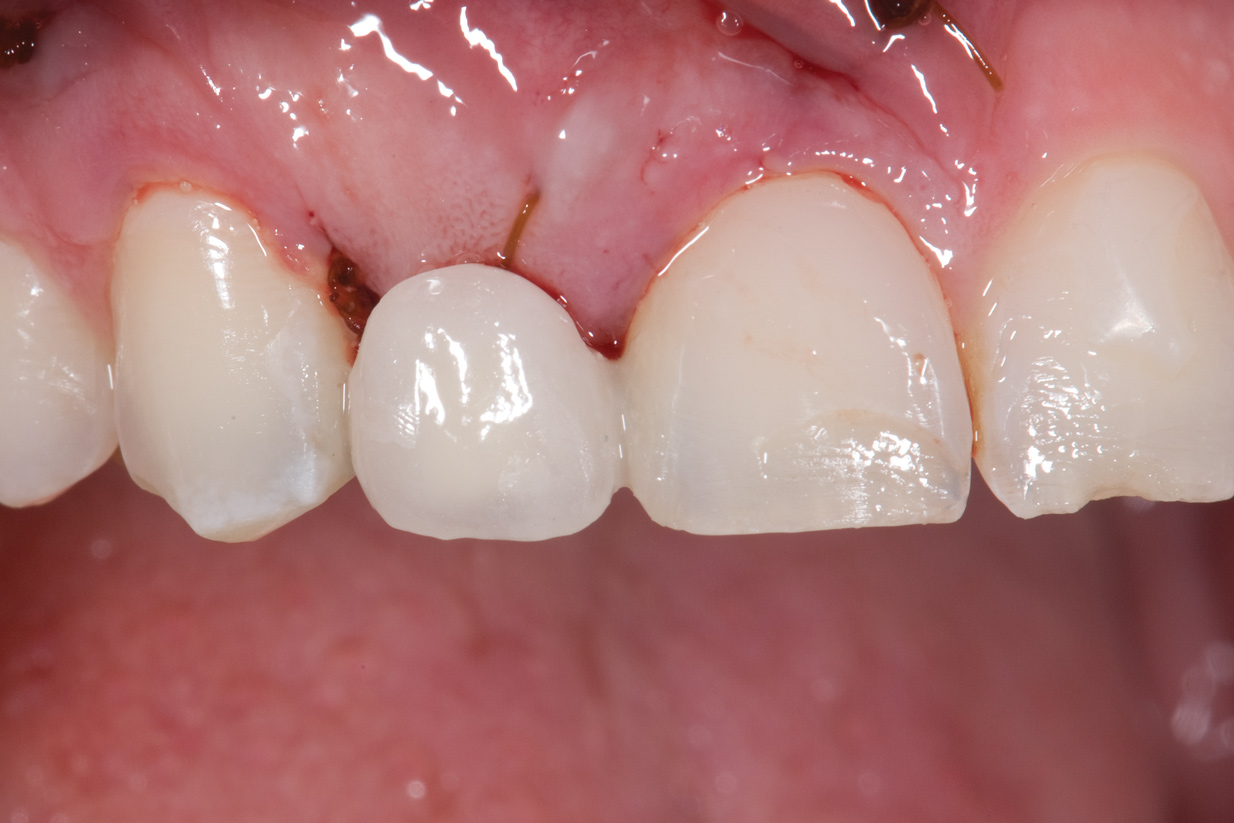

Fig 7. Resin-bonded bridge after removal, implant placement, and bridge recementation.

Figure 7

Fig 8. Resin-bonded bridge removed and CT graft completed. Bridge recemented once more. Note reduction in cervical area of pontic.

Figure 8

Six years later, the patient was in his fourth year of college when he finally returned for implant placement (Figure 6). Interestingly, the provisional bridge had not come loose since it was bonded, even though the patient had a nail biting habit and had fractured most of the resin-based composite on the central incisors. He had also failed to wear his retainer, and as a result, the upper left lateral incisor had rotated slightly (Figure 6). In the right lateral incisor site, there was a horizontal deficiency in the bone and overlying soft tissue. A cone-beam computed tomography (CBCT) image was taken, and the area was evaluated for implant placement. There was enough native bone to place a 3-mm implant, but a connective tissue graft was needed to rebuild the deficient ridge. Unfortunately, when the patient presented for implant placement, it was during a holiday break from school and he needed to study. Therefore, the patient did not want to simultaneously augment with a connective tissue graft at the time of implant placement due to the pain associated with treatment. A 3-mm-by-10-mm Astra Tech implant (Dentsply Sirona Implants, dentsplysirona.com) was placed, and the resin-bonded bridge was rebonded, utilizing the CoJet Silica, salinization, and the same dual-cured resin cement. Four months later, the patient returned for the connective tissue graft (Figure 7). The bridge was removed, the graft was performed utilizing a tunnel technique, and the bridge was rebonded as described earlier (Figure 8). After another 4 months, the patient returned during a 2-week break. At this time, the implant was exposed, the tissue was manipulated with provisionals, and the final restorative work was completed (Figure 10 and Figure 11).